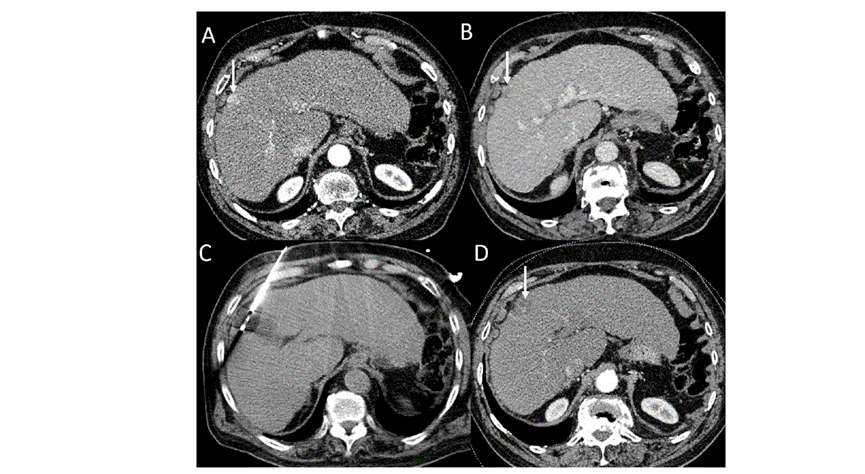

冷冻消融胆囊附近肿瘤病灶

(A)动脉期 MRI 显示胆囊附近有外周增强病变(箭头)。

(B)手术过程中 CT 显示冷冻探针位于病灶内。

(C)消融后,术后 1 个月CT 显示完全消融(箭头)。

(A)动脉期CT图像显示有一个包膜下结节(箭头)。(C) 在手术过程中的CT显示一个冷冻探针位于病灶内。随访时间中位数为7个月(范围:3-12个月),随访期间患者无局部肿瘤进展或死亡。

(A)门静脉期 CT 图像显示胆囊附近有病变(箭头)。(D)消融手术后 1 个月CT 显示完全消融。